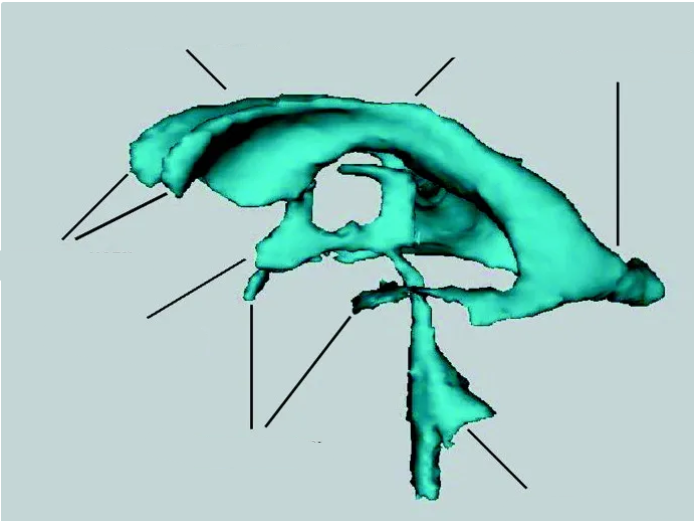

The purple hippocampus is visualized tracing the ventricular system (turquoise).